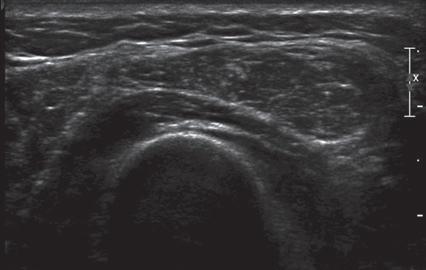

FIGURE 1.21 Spatial Compounding. Ultrasound images of the supraspinatus tendon without (A) and with (B) spatial compounding show softening of the image in B.